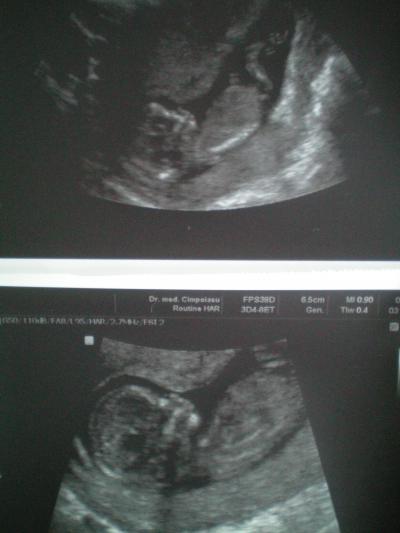

Hallo Mädls, erst einmal ein ganz großes Dankeschön an euch alle! Es tut mir jedesmal so wahnsinnig gut zu lesen dass ihr an mich denkt und mir die Daumen drückt, das hat mir total geholfen! Vielen Dank dafür! Der Termin gestern war einfach nur toll, zwar konnte ich vor lauter Demut vor dem kleinen Menschlein nicht viel sagen und die Tränchen sind gekullert, aber mein Frauenarzt ist ganz lieb und hat mir alles erklärt. Meinem Bauchbewohner geht es super! Scheint auch eine Sportskanone zu werden, jedenfalls hatte der FA anfangs ziemliche Probleme im richtigen Moment ein Bildchen zu schießen weil sich das Baby dauernd bewegt und gedreht hat. Aber das wichtigste ist ja sowieso: das Herzchen hat ganz doll geschlagen , alles ist dran und zeitgemäß entwickelt. Ich finde es so faszinierend welchen Sprung das Baby gemacht hat wenn man die Bilder der letzten beiden US vergleicht und bedenkt dass dazwischen ja "nur" 4 Wochen liegen. Ihr merkt, ich bin immer noch ganz hin und weg von MEINEM kleinen Wunder!!! Schwanger war ich ja jetzt schon etwas länger , aber jetzt langsam fange ich an das alles so richtig zu begreifen, zu fühlen und ich FREU MICH TIERISCH!!! So, jetzt aber die beiden Bilder (leider hab ich keinen Scanner und muss die Bilder abfotografieren, da leidet die Qualität ziemlich) Ich wünsche euch allen einen ganz schönen Tag! Ich hoffe ihr habt auch so tollen Sonnenschein. Bei uns steht heute Nachmittag ein Besuch bei der werdenden Ur-Oma an, die freut sich auch schon auf die neuen Bilder vom Baby. Liebe Grüße Stephie

Bild zu FA-Bericht von gestern und Bilder ;-) - Forum für September - Mamis